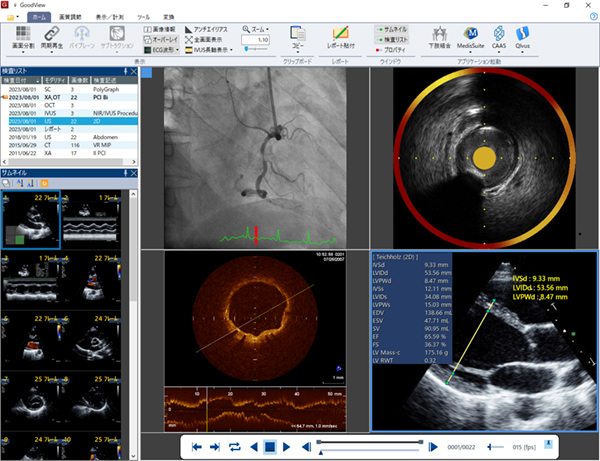

・DICOMビューワ「GoodView」シリーズ

DICOMビューワ「GoodView」は主に循環器分野で発生する画像の読影に特化した多機能ビューワです。直感的な操作で過去検査や他モダリティとの比較参照ができるのはもちろんのこと,エコー画像での容積や流速の計測,IVUS/OCT画像での長軸画像構築といった,読影を補助する機能を多数搭載しています。さらに臨床のみならず学会発表でもご活用いただけるmp4等へのファイルフォーマット変換も可能です。Goodnetの標準ビューワとしてだけでなくWindows対応単体プログラム「GoodViewPRO」としてもご提供できます。